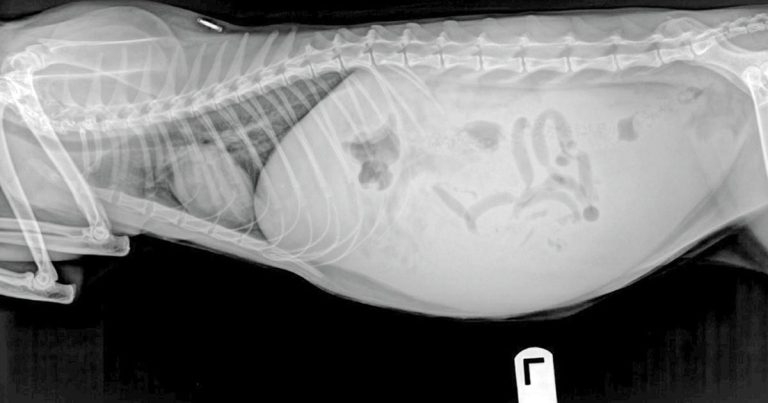

With the starting point an x-ray of a two-year-old shorthaired cat with abdominal effusion and a history if dyspnoea, lethargy and anorexia, Francesco Cian asks: what is the diagnosis?

Figure 1. An x-ray from a two-year-old domestic short-haired cat with abdominal effusion, and a clinical history of dyspnoea, lethargy and anorexia.

Figure 1 is an x-ray from a two-year-old domestic short-haired cat with abdominal effusion, and a clinical history of dyspnoea, lethargy and anorexia.